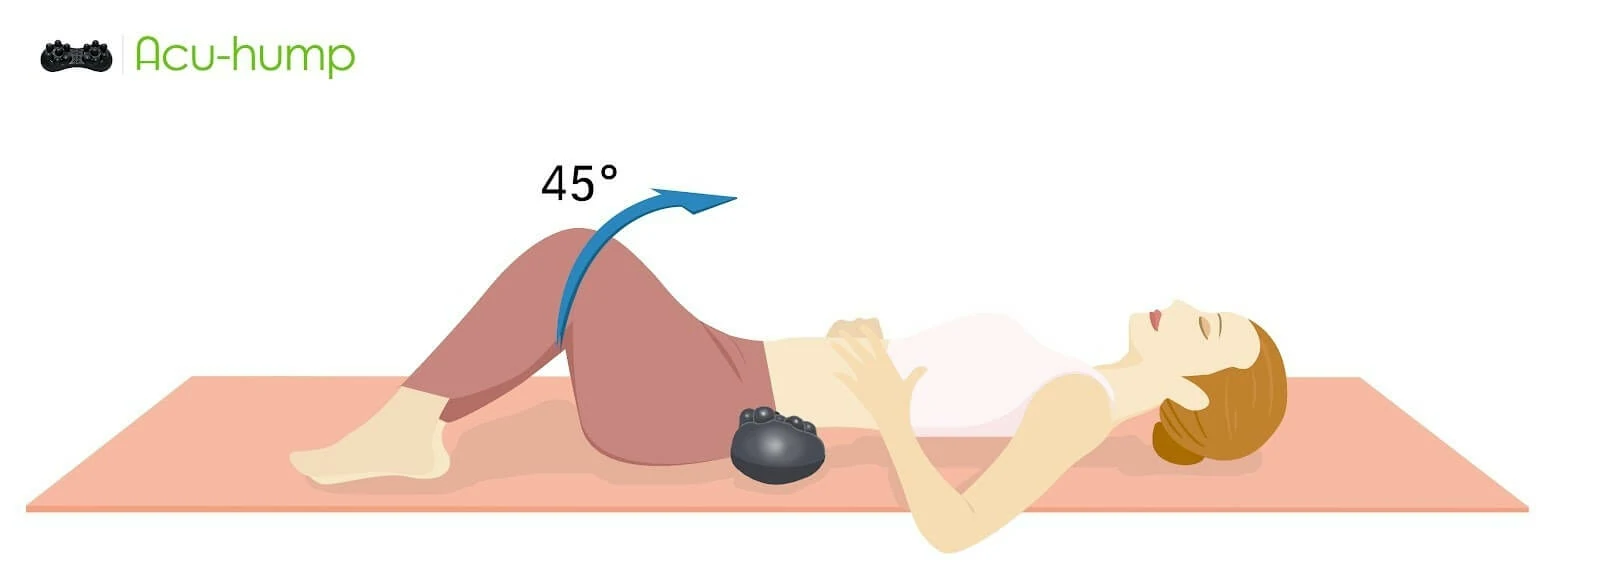

Acu-hump is an incredibly effective tool for massaging and stretching the piriformis muscle. This muscle is located deep in the buttock area and can become tight and inflamed, leading to pain and discomfort. By incorporating Acu-hump into your daily routine, you can help to release tension in the piriformis muscle and promote overall relaxation in the lower body.

Using Acu-hump to massage the piriformis muscle is simple and effective. Simply place the tool under the affected area and use it to apply pressure to the muscle. You can adjust the pressure to your liking and focus on areas that feel particularly tight or painful. The raised bumps on the tool will work to target and release pressure in the muscle, promoting relaxation and pain relief.

In addition to massage, stretching with Acu-hump can also be incredibly effective for releasing tension in the piriformis muscle. By using the tool to support and extend the muscle, you can work to increase flexibility and reduce the likelihood of injury. Regular stretching exercises can help to prevent the development of piriformis syndrome, while also promoting overall health and well-being.

Incorporating Acu-hump into your daily routine is a simple and effective way to promote relaxation and ease tension in the lower body. Whether you are dealing with piriformis syndrome or simply looking for a way to release tension and improve flexibility, Acu-hump can be a valuable tool to have in your self-care arsenal.